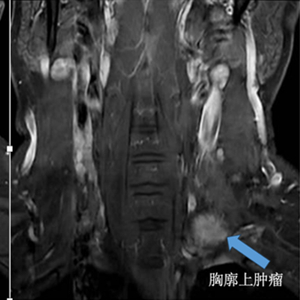

患者李哥(化名)是一名35岁的男性患者,因为连续10个月出现腰痛伴双腿酸痛的情况,到深圳市人民医院进行了CT及核磁检查。检查结果显示,李哥颈椎管内有一个呈哑铃型的异常占位,从椎管内突破至胸腔内,内小外大。

医生经过研判,考虑该异常占位为椎管内哑铃型神经鞘瘤,需尽快手术。但由于肿瘤形状特殊,传统的手术要考虑开胸手术才能切除肿瘤,需要先从李哥的椎体后方切开一个创口,先切除椎管内的肿瘤,然后再从颈部切开一个创口,切除从椎管内突出到颈部的肿瘤。这样一来,手术需要两个大切口,可能还需要分次进行手术,手术时间长,创伤大,恢复慢,对患者围术期的生活质量也有所影响。